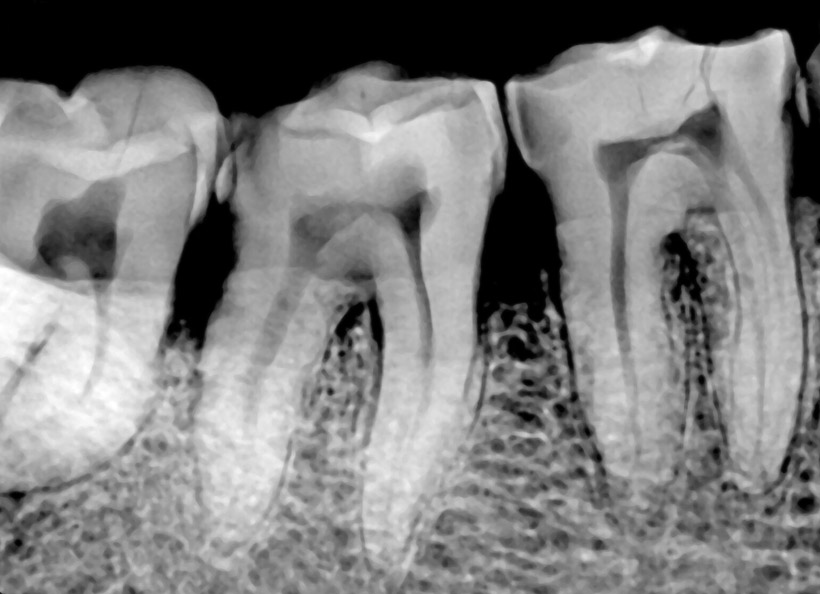

Radiografia digitală bitewing (muşcată) este o radiografie ce oferă informaţii precise (la fel ca şi radiografia retroalveolară) pe o zonă limitată a cavităţii bucale. Pe această radiografie medicul stomatolog poate vedea coroanele dinţilor, atât a dinţilor de pe maxilar, cât şi de pe mandibulă, cât şi rădăcina acestora. Este indicată în cazul cariilor interdentare, retracţiilor ososase, pungilor parodontale, etc.